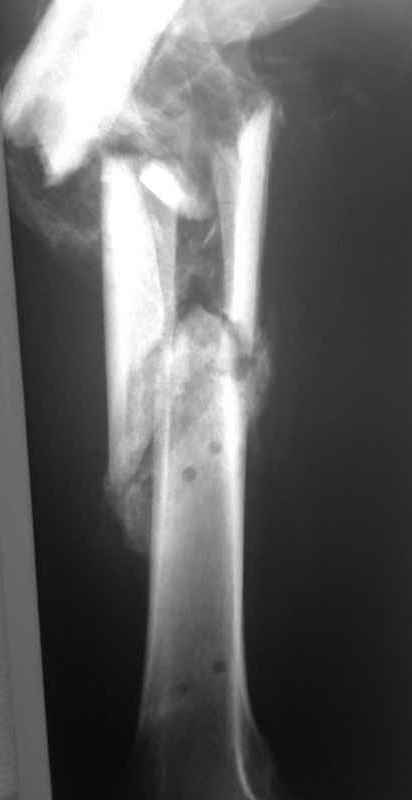

[Ortho] Неправильно срастающийся оскольчатый перелом бедра

Вложение не в текстовом формате было извлечено…

Имя     : 003.jpg

Тип     : image/jpeg

Размер  : 16020 байтов

Url     : http://weborto.net:8080/pipermail/ortho/attachments/20110406/c06e2959/attachment-0006.jpg